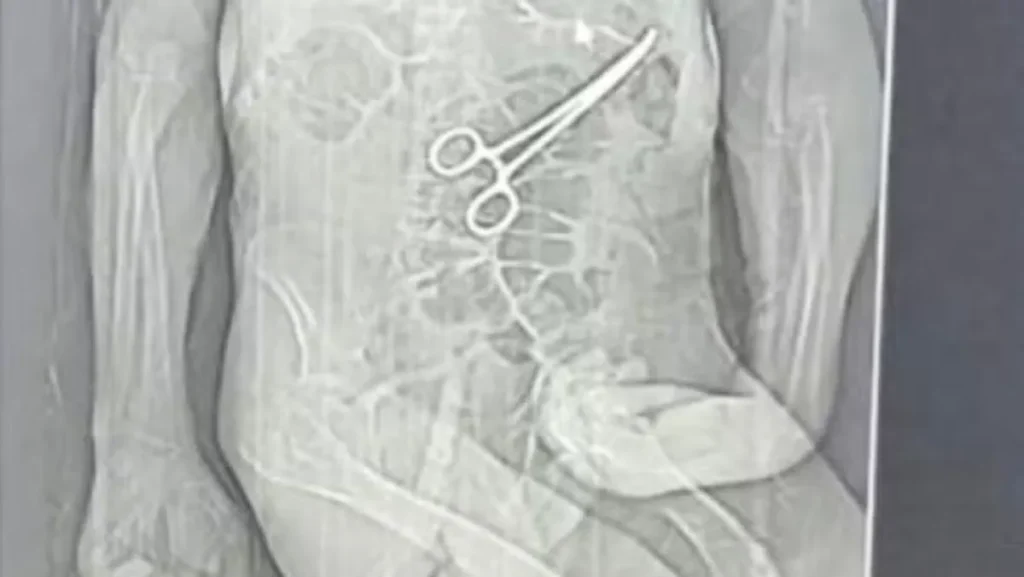

Após o incidente, a família de Manoel, alarmada com os resultados da tomografia, que teriam sido divulgados por uma emissora local, decidiu buscar medidas legais. Segundo o advogado da família, as imagens revelaram a presença do instrumento cirúrgico esquecido dentro do corpo do paciente, um fato considerado como grave pela família.

Os parentes de Manoel afirmam que a pinça cirúrgica foi deixada no corpo do paciente após a primeira cirurgia, uma omissão que, segundo eles, só foi reconhecida após a morte do idoso. A Secretaria Municipal de Saúde de João Pinheiro confirmou que houve a retirada de um objeto durante a cirurgia e justificou que Manoel já se encontrava em estado crítico, com múltiplas comorbidades. Além disso, a secretaria indicou que foram adotadas medidas para reforçar os protocolos de segurança e que a sindicância está em andamento.